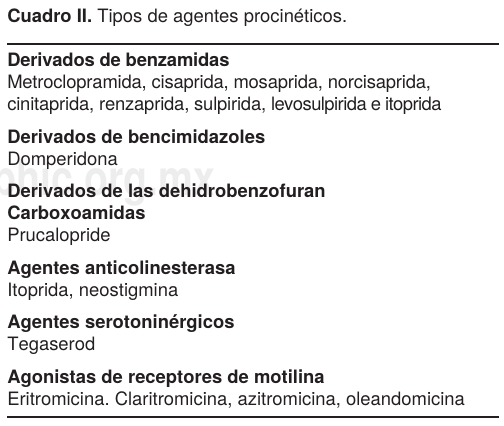

Los médicos de Urgencia, Medicina Interna y Ginecoobstetricia deben tener en mente esta patología y estar al tanto de su aparición, ya que si no se trata al inicio del cuadro clínico confirmado con estudios de laboratorio y gabinete, puede complicarse con perforación, peritonitis y muerte. Los índices de morbilidad varían en la literatura: entre más temprano se inicie el tratamiento, el porcentaje de curación es mayor hasta un 80%, si se emplean las medidas generales para este padecimiento, un esquema de fármacos procinéticos (Cuadro II) de la pasada y nueva generación,10 (mesaprida, itoprida, cinetaprida, etc.) y antibióticos según los resultados del laboratorio, por ejemplo eritromicina más neostigmina como control. Aún así, presentan un porcentaje de recidiva del 6-14%, de éstos sólo 20% llegan a ser quirúrgicos y son aquellos que recidivaron y/o llegaron con diagnóstico tardío o sin respuesta al tratamiento médico agresivo e intensivo de la descompresión con aplicación de sondas nasogástrica y rectal, corrección del desequilibrio hidroelectrolítico, control de cualquier anormalidad metabólica de fondo y descompresión endoscópica que por sus resultados buenos a excelentes (66-90%) compiten favorablemente contra una cirugía mayor, con mortalidad del (25 al 50%) y morbilidad del (3%).

El tratamiento médico general del SO comprende diversas alternativas terapéuticas (Figura 3), desde medidas generales poco invasivas hasta la utilización de la descompresión colónica por colonoscopia y cirugía. Frecuentemente se inicia con ayuno (reposo intestinal), sonda nasogástrica y rectal, enemas evacuantes, cambios posturales, tratamiento de la enfermedad de origen, reposición hidroelectrolítica y supresión de drogas potencialmente implicadas en el desarrollo del síndrome.9,10-15 El tratamiento farmacológico más recomendado actualmente en SO es para corregir el desequilibrio del sistema autónomo de la motilidad colónica,5,10-12,16,19 basados en este hecho, se han utilizado actualmente la cinitaprida, la mesaprida y la itoprida,34 por su acción procinética sobre el colon, y su potente acción selectiva sobre los receptores 5-HT4, 5-HT2 y D2 produciendo liberación de acetilcolina en los plexos mientéricos (Cuadro IV).